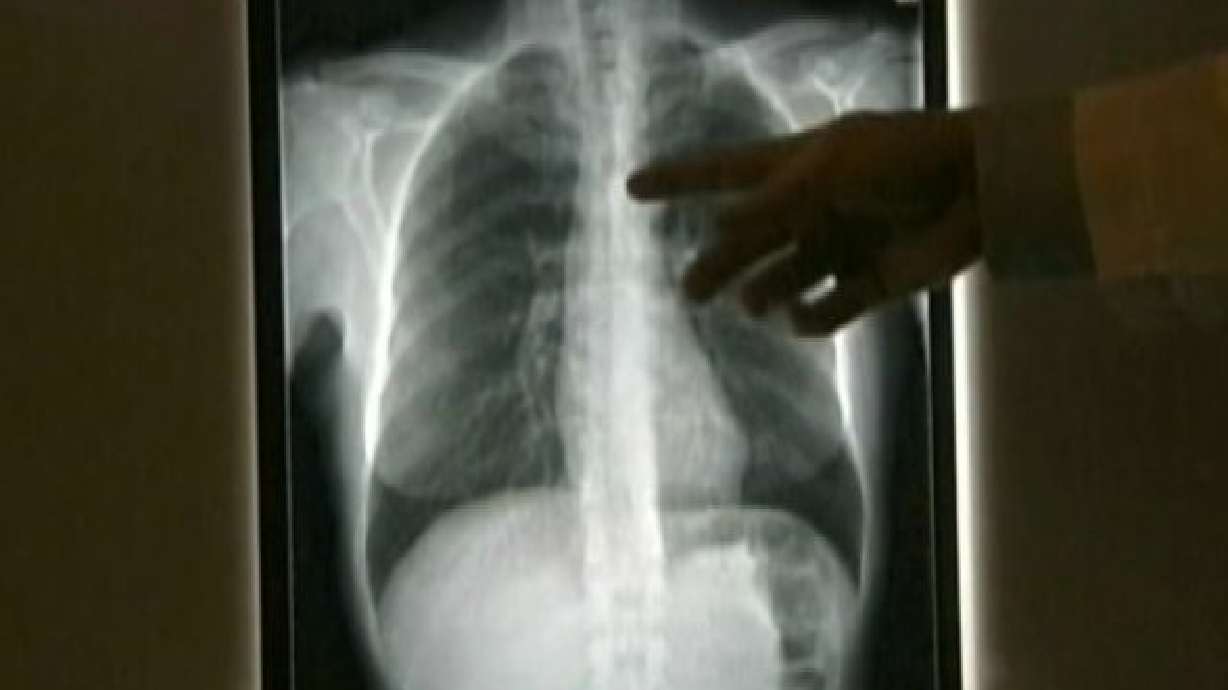

Mixon is part of a troubling trend, according to Piedmont Atlanta thoracic surgeon Dr. Saeid Khansarinia.

"We're seeing more and more lung cancer in people who don't smoke, especially women," Dr. Khansarinia said.